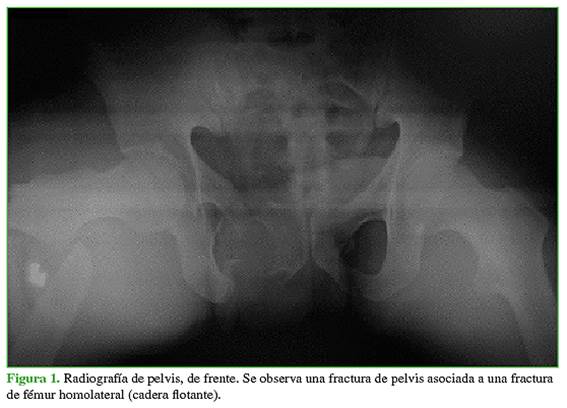

El término “flotante” relacionado con alguna articulación indica una disrupción esquelética por encima y por debajo de ella, que puede ser intrarticular o extrarticular. Este término fue introducido por Blake y McBryde, en 1975, para describir la rodilla flotante.1 En nuestro caso, nos referimos a una situación poco común en la que están involucradas una fractura de fémur con una fractura de pelvis o de acetábulo homolateral y que requerirán un tratamiento quirúrgico específico en forma secuencial (Figuras 1 y 2).2

Luego de la revisión primaria y la reanimación inicial según el protocolo ATLS con la estabilización transitoria de la fractura mediante tutores externos, se programó la osteosíntesis (Figuras 3-5).